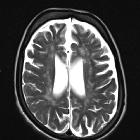

Magnetic

Resonace Imaging findings in a case of infantile Refsum disease. Axial and coronal (c-d) T2-weighted images confirm white matter changes in the supratentorial periventricular areas and in the cerebellum.